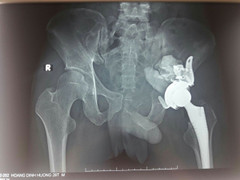

Khối u ở vùng cổ cối xương chậu khiến nam bệnh nhân bị đau khớp háng trái, tình trạng bệnh nặng hơn qua nhiều ngày khiến anh không chủ động đi lại được mà phải chống nạng.